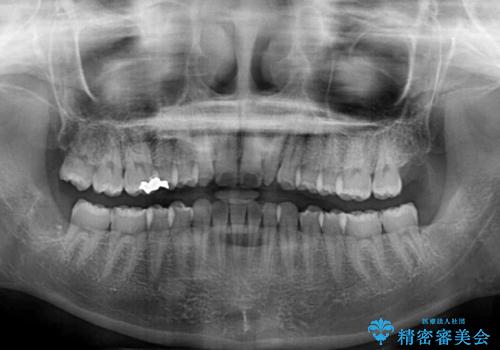

- 1年後に海外に転居するため、気になる前歯を矯正治療で整えたいとのことで来院された患者様です。

下顎は叢生が強かったため、奥歯までワイヤーを装着し、上顎は前歯の一部のみ気になっていたので、その部分にだけワイヤー装置を装着することとしました。